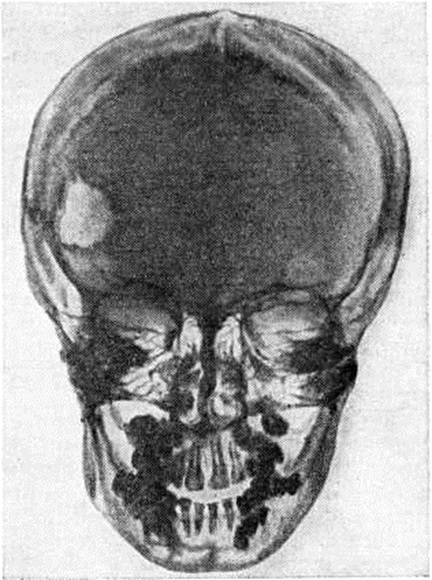

Рентгенологические картина характеризуется преимущественным поражением костей черепа (рисунок 2), таза, реже в процесс вовлекаются позвонки, ребра и длинные трубчатые кости (бедренные, плечевые, кости голени). В костях свода черепа образуются множественные дефекты неправильно округлой или овальной формы с чётко очерченными изъеденными контурами без признаков остеопороза и реактивных склеротических изменений по периферии. Размеры очагов варьируют, иногда очаги занимают обширные участки кости. Деструктивные процессы в области пирамиды, сосцевидного отростка и других отделов височной кости являются причиной поражения уха. Турецкое седло, как правило, не изменено. В ряде случаев выявляется небольшое его уплотнение. Из костей лицевого черепа изменения чаще обнаруживаются в челюстях, особенно в верхней. При поражении альвеолярных отростков наблюдается расширение зубных альвеол. В области таза очаги деструкции локализуются преимущественно в крыльях подвздошных костей. Поражение позвонков чаще бывает одиночным, встречается преимущественно в средней и нижней части грудного отдела позвоночника. Иногда развивается компрессия тел позвонков с образованием платибрахиспондилии (смотри полный свод знаний: Позвоночник) при сохранных межпозвоночных дисках. В редких случаях патологический перелом позвонка может быть первым клинические, признаком болезни. Трубчатые кости вздуваются изнутри, содержат множественные очаги деструкции различной величины, корковое (компактное) вещество истончено, секвестров не наблюдается. При субкортикальном расположении очагов могут возникнуть периоститы (смотри полный свод знаний).